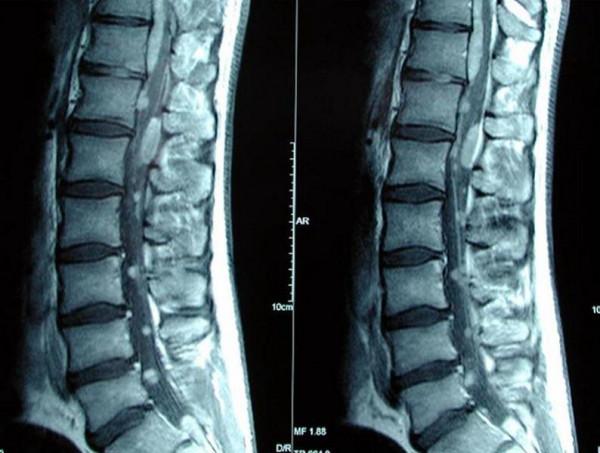

A 26-year-old man of Polish origin presented with a ten-day history of pain in the left leg and lower back. This was followed by difficulty in urinating and a decrease in sensation in both legs. Examination revealed pyramidal signs and mild weakness in both lower limbs. He had early sphincter involvement requiring catheterization. Magnetic resonance imaging of the brain was normal. However, that of the spinal cord revealed multiple intradural spinal lesions, both intra- and extramedullary, extending from the cervical cord down to the cauda equina roots. T12-L1 laminectomy was performed. Multiple intradural, extra- and intra-medullary tumors were seen. After the operation, the patient deteriorated with a sensory level at T4. Post-operative cranio-spinal radiotherapy was administered but there was no clinical improvement in the lower limbs.

Primary spinal ependymomatosis is a rare phenomenon involving multiple spinal segments in the absence of a primary intracranial tumor. Radical excision is unrealistic in this condition. Biopsy followed by radiotherapy is the preferred method of treatment.